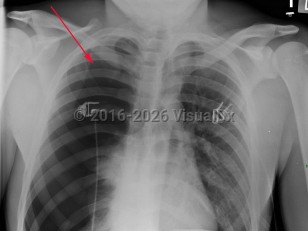

EVALI

Pneumothorax